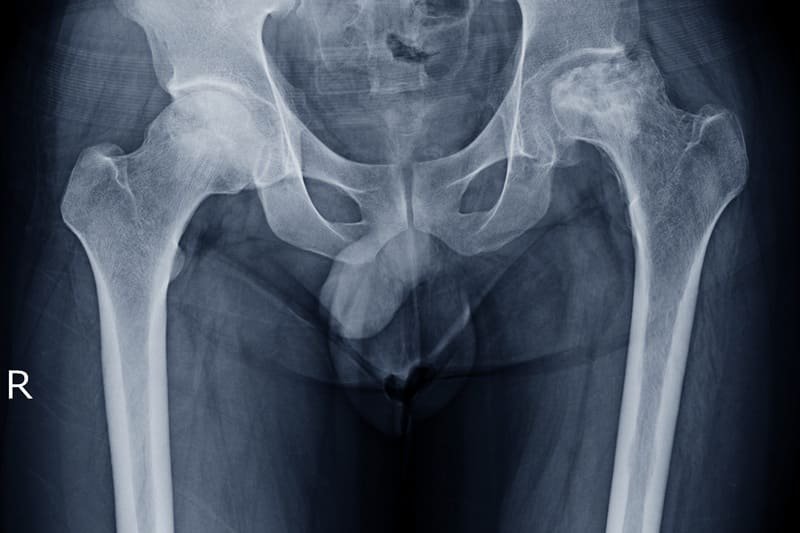

La Radiografía de fémur en Guadalajara, Jalisco es un estudio esencial para evaluar el hueso más largo del cuerpo y detectar fracturas, fisuras, lesiones traumáticas o alteraciones óseas. Es especialmente importante en caídas, accidentes o dolor intenso en muslo y cadera. La Radiografía de fémur en Guadalajara, Jalisco se realiza a domicilio con equipo portátil moderno, ofreciendo imágenes digitales claras y un diagnóstico oportuno sin necesidad de trasladarse a hospitales.

La Radiografía de fémur en Guadalajara, Jalisco se recomienda cuando existe dolor persistente en la pierna, inflamación, dificultad para caminar o sospecha de fractura tras un golpe fuerte. También se solicita en controles postoperatorios o para seguimiento de enfermedades óseas. Realizar la Radiografía de fémur en Guadalajara, Jalisco en casa es ideal para pacientes con movilidad limitada, adultos mayores o personas que requieren atención rápida y segura.

Sí, la Radiografía de fémur en Guadalajara, Jalisco permite identificar fracturas, fisuras o alteraciones óseas con alta precisión. Es una herramienta clave para diagnóstico temprano y seguimiento médico en lesiones traumáticas.